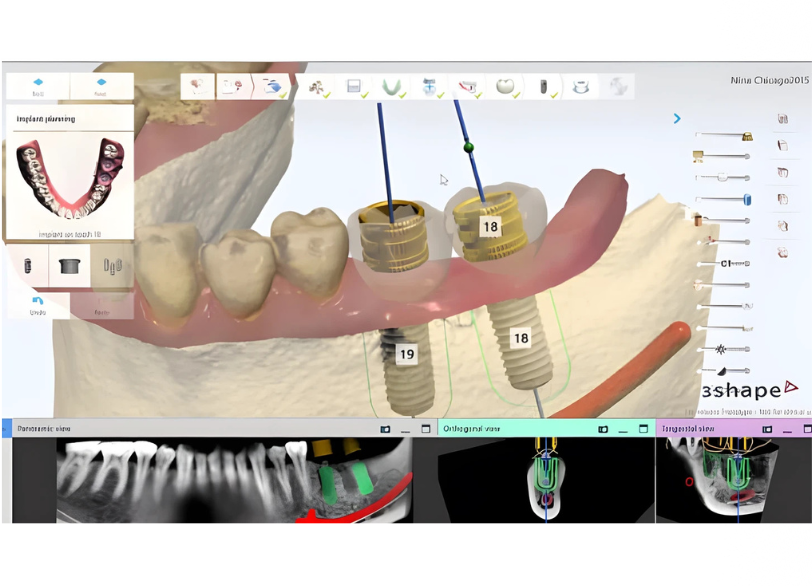

安全で長持ちするインプラント治療には、精密な診断と治療計画が欠かせません。いばた歯科では、

- 歯科用CTによる三次元診断

- 口腔内スキャナーによるデジタル分析

を用いて、骨量・骨質・神経の位置・噛み合わせを正確に把握します。

■ 精密診断で行うこと

- 安全な埋入位置の決定

- 将来の噛み合わせまで考慮した設計

- 周囲の歯・歯ぐきへの影響評価

これにより、無理のない・長期安定を目指した治療が可能になります。

CTデータとスキャナーデータを統合した精密診断

次に行うのが、歯科用CTデータ(DICOMデータ)と、口腔内スキャナーデータの統合です。

- CT

骨の量・質、神経や血管の位置を把握 - スキャナー

歯・噛み合わせ・補綴の設計情報

これらを統合することで、

- 骨の中の安全な位置

- 噛み合わせを考慮した理想的なインプラントポジション

- 将来の補綴物を見据えた埋入角度・深さ

を、三次元的にシミュレーションします。経験や勘に頼るのではなく、データに基づいた診断と設計を行うことが、インプラント治療の精度と安全性を大きく左右します。